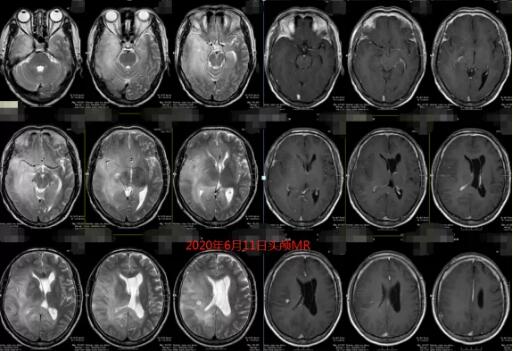

1年前,被“癫痫”折磨怕了的萧先生来到广东三九脑科医院寻求进一步治疗。当时我院头颅MR提示:右侧大脑半球及左侧颞叶、左侧侧脑室周围、胼胝体弥漫大片状异常信号影。

6月初,患者住进了我院神经外五科。此时,他的头颅MR检查提示:颅内脑实质多发病变,以右侧大脑半球较著,考虑弥漫性星形细胞瘤可能性大(其中右侧基底节区-放射冠、右侧顶叶占位性病变)。

对比1年前在我院做的影像资料,病灶范围明显增大,几乎“占据”整个右半边脑!